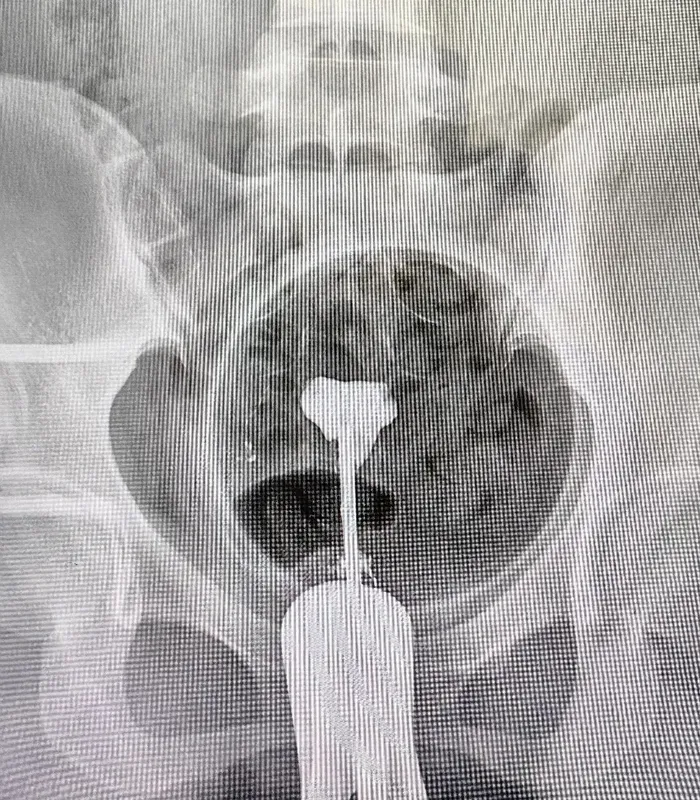

今天有位病人40歲,問:“我要做輸卵管造影,你們醫(yī)院做嗎?”我回:“做?。〔贿^,您為什么要做輸卵管造影???”病人說:“XX上說的,輸卵管造影能幫助懷孕?!蔽一兀骸澳鷳?yīng)該先清楚什么是輸卵管造影。輸卵管造影就是將通液管植入宮腔,經(jīng)過通液管注入造影劑,通過X線觀察子宮腔和輸卵管腔的影像學(xué)表現(xiàn),間接判斷宮腔形態(tài)和輸卵管通暢度;并通過造影劑在盆腔彌散速度和程度,判斷盆腔粘連情況。因而,其全稱為子宮輸卵管造影(HSG)。顯然,它是一種侵入性、診斷性檢查措施?!蔽依^續(xù)回:“既然是一種診斷性檢查,就有其適應(yīng)證和禁忌癥。一般來說,HSG的適應(yīng)證有:1.懷疑輸卵管阻塞和其他損傷(粘連、阻塞、閉鎖、瘺管),2.懷疑子宮結(jié)構(gòu)異常(雙角、鞍形子宮、子宮發(fā)育不全、宮腔隔、粘連),3.粘膜下子宮肌瘤、子宮內(nèi)膜息肉和其他腫瘤,4.懷疑子宮異物、損傷、輸卵管破裂,5.懷疑子宮內(nèi)膜異位癥、結(jié)核、子宮內(nèi)膜增生和其他子宮和輸卵管疾病,6.懷疑輸卵管發(fā)育不全或結(jié)構(gòu)異常等。同時(shí),在某些情況下是不能做HSG的,即禁忌癥。常見的禁忌癥有:1.妊娠期不能做,疑似懷孕也不能做,2.對(duì)造影藥物過敏者也不能做,3.陰道、子宮、輸卵管或卵巢的急性炎癥期不能做,4.異常子宮出血也屬于禁忌癥,5.腎、肝、心力衰竭急性期不能做,6.傳染病活動(dòng)期和甲狀腺機(jī)能亢進(jìn)者也不能做?!辈∪苏f:“哦,還那么復(fù)雜?。?!不會(huì)有危害吧?”我回:“復(fù)雜算不上,不過,凡事均有利弊。既然HSG被推薦為評(píng)估輸卵管通暢性的首選方法,它的優(yōu)勢(shì)是明顯的,如:簡便、易行、廉價(jià)、安全,不過,也有一定的假陽性和假陰性結(jié)果。但,總體上來說,造影后不論采用何種治療手段,期待治療、宮腹腔鏡手術(shù)或是輔助生殖技術(shù),均可以明顯增加患者妊娠概率。除評(píng)估輸卵管通暢度以外,HSG還可以間接評(píng)估輸卵管蠕動(dòng)功能、拾卵功能及盆腔環(huán)境。同時(shí),其劣勢(shì)也是挺明顯的,除了假陽性和假陰性結(jié)果外,還有可能因器械損傷而出血,或因感染致腹痛、發(fā)熱,也會(huì)有子宮穿孔、血管破裂、迷走神經(jīng)興奮引起的暈厥等少見并發(fā)癥發(fā)生。另外,X線的輻射作用影響卵巢功能,HSG后三個(gè)月內(nèi)不宜懷孕,避免對(duì)子代產(chǎn)生不良影響;最容易被忽視的是造影藥物對(duì)輸卵管粘膜的損傷?!辈∪藛枺骸凹訇栃?、假陰性是啥意思?”我回:“假陽性,就不是真陽性。例如,輸卵管本是通暢的,因?yàn)榫o張而出現(xiàn)輸卵管痙攣,導(dǎo)致造影劑未能進(jìn)入輸卵管,影像學(xué)上就表現(xiàn)為輸卵管梗阻、不通暢。就是假陽性,而非真陽性。同理,假陰性就不是真陰性,例如輸卵管本來是不通暢,結(jié)果因有血管破裂,造影劑直接進(jìn)入血管,影像學(xué)上也表現(xiàn)為通暢,就是假陰性,而非真陰性。不過,假陽性、假陰性的幾率不是很大?!辈∪苏f:“那我還得考慮考慮,看來也不是百分之百有幫助?。 ?/p>

在我國做子宮輸卵管造影,所用的造影劑有碘水和碘油二種,其中,絕大部分醫(yī)院是用碘水做造影,所占比率在80%以上,而只有小部分不到20%的醫(yī)院用碘油造造影。在做子宮輸卵管造影檢查時(shí):所用造影劑為碘油,當(dāng)出現(xiàn)靜脈和淋巴管逆流時(shí),立即停止造影檢查是對(duì)的。因?yàn)榈庥秃脱翰荒芟嗳莼旌弦黄?,碘油?dú)立成形。當(dāng)較多碘油進(jìn)入盆腔靜脈和淋巴管后會(huì)進(jìn)入下腔靜脈,進(jìn)入右心房,進(jìn)而進(jìn)入肺動(dòng)脈,可形成肺栓塞,危及被檢查者生命安全。但是,當(dāng)所用造影劑為碘水,出現(xiàn)靜脈和淋巴管逆流時(shí),可以繼續(xù)造影檢查,直至滿足臨床診斷后再結(jié)束檢查。因?yàn)榈馑脱嚎梢韵嗳輹?huì)混合一起,不會(huì)形成栓塞,因此,碘水逆流進(jìn)入靜脈和淋巴是安全的。大家好多做過CT增強(qiáng)檢查,成年人一般需要用高壓注射器要向靜脈內(nèi)快速注入100毫升碘水進(jìn)行檢查,這么大的量,又這么快速進(jìn)入靜脈都是安全的。子宮輸卵管造影,一般注入宮腔內(nèi)碘水造影劑不會(huì)超過10毫升,即使這些造影劑都進(jìn)入靜脈也是安全。下面這二例,一例碘油輸卵管造影,是一家上海著名大學(xué)附屬婦產(chǎn)醫(yī)院放射科做的,出現(xiàn)明顯的碘油逆流進(jìn)入右卵巢靜脈和淋巴管,本應(yīng)該立即停止造影檢查,但是卻沒有停止檢查,而是完成了造影檢查。導(dǎo)致這位不孕者造影后坐立難安、劇烈疼痛2個(gè)多小時(shí)。這算是非常幸運(yùn)的了,沒有出現(xiàn)更嚴(yán)重情況。另外一例為碘水造影,就是優(yōu)維顯(碘普羅胺注射液)子宮輸卵管造影,是一家省婦幼保健院放射科做的,當(dāng)宮腔兩側(cè)出現(xiàn)靜脈和淋巴逆流時(shí)就中止了造影檢查。本應(yīng)該繼續(xù)造影檢查,最終滿足診斷需要后再結(jié)束檢查。可他們確停止造影檢查,未能完成檢查,不能給出正確診斷。第一例碘油造影,出現(xiàn)靜脈逆流該立即停止造影,卻沒有停止造影第二例碘水造影,出現(xiàn)靜脈逆流不該停止造影,卻停止造影,影響診斷和治療?再次強(qiáng)調(diào):在做子宮輸卵管造影檢查,造影劑為碘油,出現(xiàn)靜脈和淋巴管逆流時(shí),應(yīng)立即停止造影檢查,防止碘油造成肺栓塞,保護(hù)生命安全是正確的。當(dāng)用造影劑為碘水,出現(xiàn)靜脈和淋巴管逆流時(shí),可以繼續(xù)檢查,直至滿足臨床診斷后再結(jié)束檢查。醫(yī)生臨床工作中,做事要知其然,更要知其所以然。不能,人云亦云。錯(cuò)誤的檢查方式,不僅不能進(jìn)行正確診斷,影響治療;而且還有可能對(duì)患者生命和財(cái)產(chǎn)等造成危害。